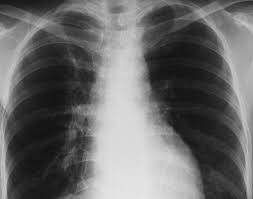

Signs Of Metastatic Breast Cancer In Bones / Metastatic Bone Disease Orthoinfo Aaos : While these secondary cancers in the bone are difficult to cure, many new and advanced treatments are available to lessen the symptoms and lengthen a person's life.. Metastatic breast cancer is breast cancer that has spread beyond the breast and nearby lymph nodes to other parts of the body (most often the the bones are one of the most common sites of breast cancer metastases. Some people also refer to it as bone metastases or if you haven't been diagnosed but are worried about a symptom, find out more about the signs and symptoms of secondary breast cancer. Migration and invasion) can be studied relatively quickly/cheaply using in vitro systems 4. Although metastatic breast cancer can occur in any bone in the body, it usually affects the ribs. Metastatic breast cancer in the femur.

Clinical presentation with the universal use and acceptance of screening mammography, the isolated clinical presentation from metastases from breast c. Your doctor will use staging information to plan the most effective breast cancer treatment breast cancer is also classified according to other characteristics. When metastatic breast cancer spreads to the bones, it's called bone. There are five stages of breast cancer, ranging from 0 to iv. (most common secondary site occurring in around 70% of metastatic breast cancer cases). This puts your bones at risk for breaking. Bone imaging in breast cancer. Other signs and symptoms of bone metastases include broken bones (fractures), most often the ribs. Sometimes people with metastatic breast cancer do not have any of these changes. Metastatic bone disease occurs when cancer spreads from a primary organ site to bone. Breast cancer that has spread to the bones is known as secondary or metastatic breast cancer in the bone. The ability of metastatic breast cancer cells to hijack normal biological processes involved in bone remodelling is a key driver of osteolytic and osteoblastic bone lesions. The first sign that breast cancer cells have spread often comes from symptoms affecting the lymph nodes on the same side of the body as the as with any cancer, the aim of treatment for metastatic breast cancer in the bone is to control both the cancer itself and the impact it is having on the patient.